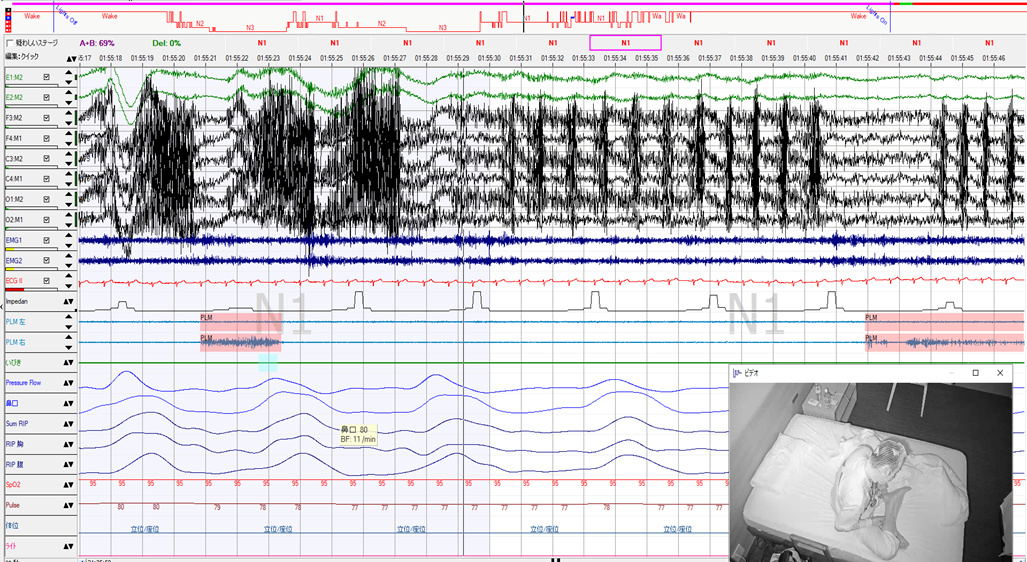

異常行動発現時のPSG波形です。

ビデオ映像からは、マイスリーの副作用である夢遊症状と思われるような異常行動を認めています。

仰臥位で呼吸イベントが出現すると、苦しいのか突然座位になり体を揺らしながら首を垂れており、しばらくすると普通に横になっています。

また呼吸苦が誘因となっているので、まずは無呼吸の治療でこの異常行動は抑えられるかもしれません。上記の波形は30秒エポックです。脳波波形は座位になったことで筋電図が重畳し、判定不能でした。

てんかん発作時と同様、朦朧状態の時の睡眠段階判定ルールはありません。覚醒とはせずにN1して、あとはコメントで補っています。